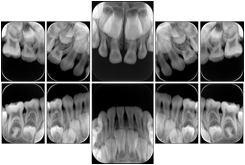

Intra-oral radiography typically involves acquisition of multiple images of various parts of the dentition. Many digital radiographic systems offer customized templates that are used for displaying the images in a study on the screen. These templates may also be referred to as mounts or view sets. The Structured Display Object represents a standard method of encoding and exchanging the layout and intended display of Structured Displays. A structured display object created in this manner could be stored with a study and exchanged with images to allow for complete reproduction of the original exam.

1. A patient visits a General Dentist where a Full Mouth Series Exam with 18 images is acquired. The dentist observes severe bone loss and refers the patient to a Periodontist. The 18 images from the Full Mouth Series along with a Structured Display are copied to a DICOM Interchange CD and sent with the patient to see the specialist. The Periodontist uses the CD to open the exam in his Dental Radiographic Software and consults via phone with the General Dentist. Both are able to observe the same exam showing the images on each user's display using the exact same layout.

Intra-oral Full Mouth Series Structured Display

Figure OO-1. Intra-oral Full Mouth Series Structured Display